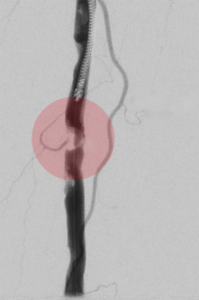

3. Stentimplantation – Einsetzen eines Stentes/ Gefäßstütze

Nach der Gefäßweitung kann durch Einrisse in den inneren Ablagerungen oder durch die Elastizität der Gefäßwand die Weitung nur ungenügend erfolgreich sein. Zur Stabilisierung des Befundes wird dann in diese Gefäßregion ein Stent eingesetzt. Dieser besteht aus einem feinen starren oder flexiblen Edelmetallgeflecht und kann auch mit Medikamenten gegen die Arteriosklerose oder zur Verhinderung der Bildung von Blutgerinnseln beschichtet sein.

Unter bestimmten Bedingungen, v.a. bei Verletzungen der Gefäße mit daraus resultierender Blutung oder lokalen Gefäßerweiterungen, werden Stents mit einer Ummantelung eingesetzt, die die Gefäßwand abdichten oder die Erweiterung überbrücken.